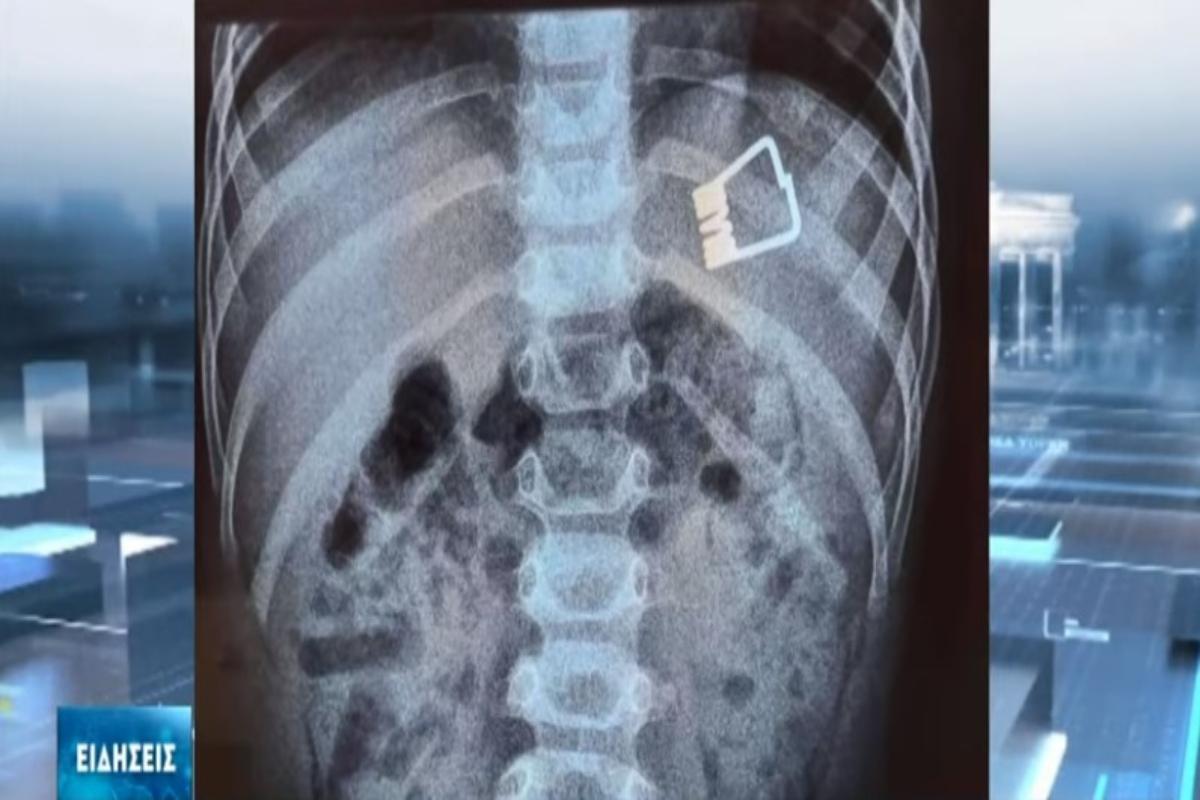

Οι γιατροί κατάφεραν να βγάλουν το μανταλάκι από τον οργανισμό του παιδιού χωρίς χειρουργική επέμβαση, παρά με τη βοήθεια ενός ενδοσκοπίου τελευταίας γενιάς.

Σύμφωνα με το ρεπορτάζ της ΕΡΤ, το παιδί κατάπιε το μανταλάκι στο σπίτι του και στη συνέχεια μεταφέρθηκε με Super Puma από τη Λήμνο στη Θεσσαλονίκη, όπου το ανέλαβαν οι παιδίατροι.

«Όταν το παιδί έφτασε εδώ αμέσως κινητοποιηθήκαμε, ενημερώσαμε τους αναισθησιολόγους, είχαμε έτοιμο το χειρουργικό κρεβάτι. Το παιδί έπρεπε είναι νηστικό 6 με 8 ώρες και προβήκαμε στην αφαίρεση ενδοσκοπικά του ξένου σώματος», δήλωσε ο Ιωάννης Ξηνίας, αναπληρωτής καθηγητής Παιδιατρικής Γαστρεντερολογίας.

Το παιδί επέστρεψε στη Λήμνο και χαίρει άκρας υγείας.